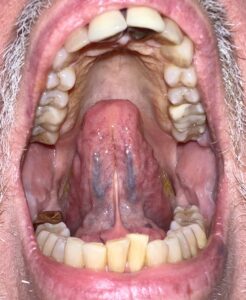

Tongue-Tie Release Using CO2 Laser Technology

Tongue-tie, also known as ankyloglossia, is a condition present at birth that restricts the tongue’s range of motion. With tongue-tie, an unusually short, thick, or tight band of tissue (lingual frenulum) tethers the bottom of the tongue’s tip to the floor of the mouth.

This tethered band of tissue prevents the tongue from functioning properly during swallowing causing a low tongue posture which eventually leads to airway and posture problems, snoring, TMJ symptoms, neck tension and forward head posture. We know that the tongue has many functions including playing a role in talking, chewing, and swallowing. The resting position of the tongue in the palate is the primary stimulation for midface growth and development and provides the stabilization for the cranial base as well as contributing to normal cranial motion. During the swallowing process, the upward pressure to the tongue into the hard and soft palate drains the sinuses and middle ear and increases the cranial rhythmic movement by increasing motion at the sphenobasilar symphysis. The tongue is also intimately connected to the hyoid bone, lower jaw and temporal bones via muscles and ligaments. When the tongue is resting in a low posture in the lower jaw, the head nods forward following the posture of the tongue, leading to a forward head posture, forward rolling of the shoulders, and a forward tilt of the pelvis along with the inward collapse of the feet.